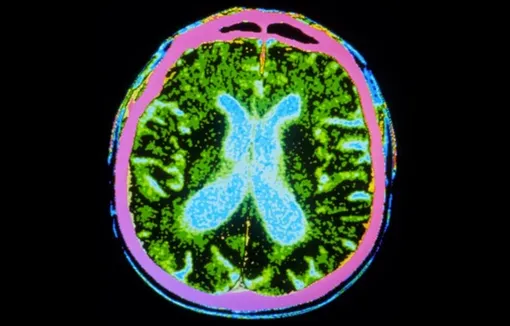

Непосредственно перед операцией клетки были разморожены и введены в структуру глубокого мозга — путамен (или скорлупа), которая является важной областью связей между моторными нейронами. Нейроны, связанные с путаменам, как раз и гибнут при болезни Паркинсона,.

Стволовые клетки вводили в 18 участков по всему путамену в обоих полушариях — «чтобы заполнить эту область мозга», говорит Вивиан Табар, нейрохирург из Мемориального онкологического центра имени Слоуна-Кеттеринга в Нью-Йорке, которая проводила операции в США.